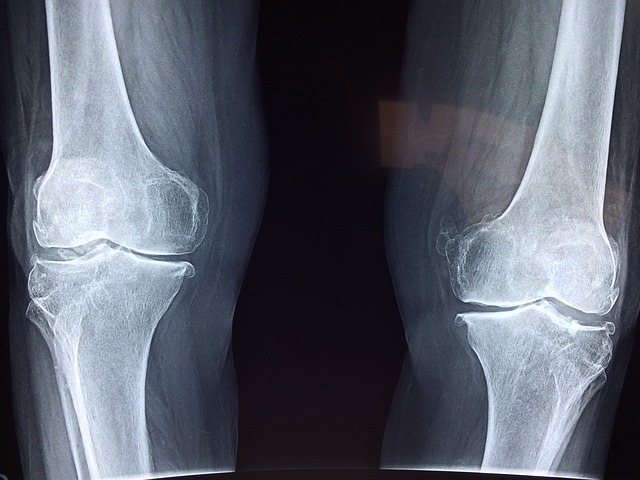

2. 뼈 건강 증가

여러가지 방법으로 뼈 건강을 증진시키고, 골절 치유 속도 높인다고 합니다. 또한 뼈의 손실을 감소시켜서, 골다공증 및 기타 뼈 관련 질병 예방한다고 합니다.

- 11주간 쥐를 대상으로 진행한 연구에 따르면 시서스가 신체의 뼈 대사에 관여하는 단백질 수준을 바꿔서 뼈 손실을 예방한다고 밝혀짐.

- 6주동안 하루 3번 500mg을 복용하면, 골절된 턱뼈의 치유 속도를 높이는 것이 증명 되었고, 또한 통증과 붓기도 줄이는 것으로 확인되었음.

- 유사한 다른 연구에서도 3개월간 매일 1200Mg 복용 시 골절 치유가 촉진되고 뼈 형성에 필요한 단백질 수치가 증가되는 것 확인.